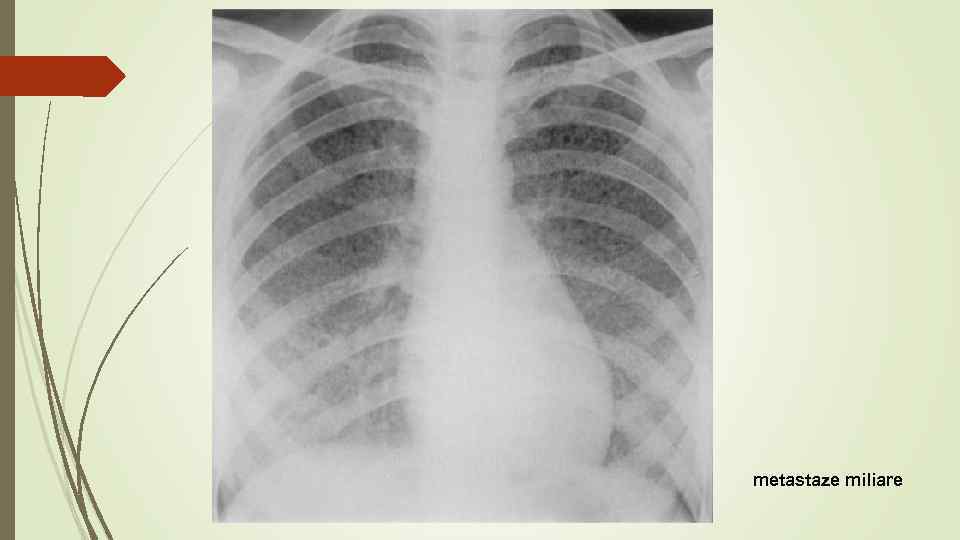

metastaze miliare

metastaze miliare